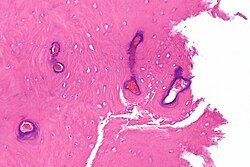

| Chondroma | ctyologically benign cells | equally spaced nests | usu. diaphysis | benign / DDx: chondroma, well-diff. chondrosarcoma | IHC / bone marrow cavity chondroma = enchondroma | File:Enchondroma - very high mag.jpg Enchondroma. (WC) |

| Chondrosarcoma | cartilaginous appearance +/- nuclear atypia | lack osteoid, if present -> osteosarcoma | usu. diaphysis, classically hip; almost never distal extremity | >40 years old | IHC / may be histologically benign looking | File:Chondrosarcoma (2).jpg Chondrosarcoma. (WC) |